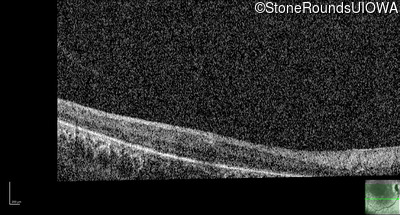

Optical Coherence Tomography - Right - No Light Perception

Exemplar / OCT Stack